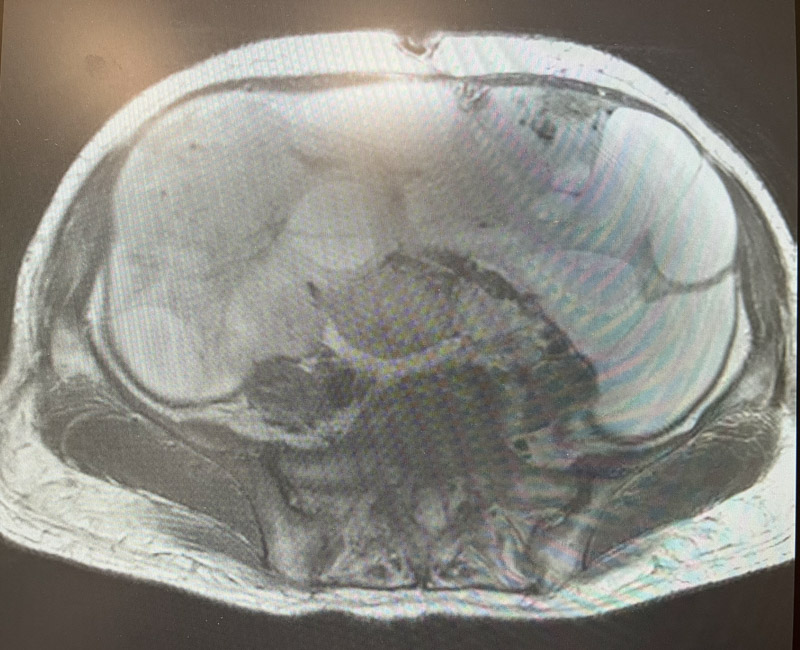

婦科二病區(qū)主任陳煜岊認(rèn)真詢問病史,并為患者進(jìn)行專科檢查。B超提示于盆腹腔見一186mm×117mm巨大囊實(shí)性腫物,上至劍突下,右至腋前線,左至腋中線。

由于患者已出現(xiàn)腹脹痛、進(jìn)食差、心慌等壓迫癥狀,而且不能排除腫物是惡性腫瘤的可能,如不及時手術(shù),腫物進(jìn)一步增大,可能出現(xiàn)腫物破裂、感染、惡性腫瘤轉(zhuǎn)移等情況。

經(jīng)過詳盡周密的術(shù)前評估及準(zhǔn)備,在麻醉科的仔細(xì)的監(jiān)護(hù)下,婦科手術(shù)團(tuán)隊開始進(jìn)行手術(shù),雖然已有心理準(zhǔn)備,但看到腹腔內(nèi)的巨大腫物還是讓所有人感到震驚。手術(shù)過程中,進(jìn)行的每一步都如履薄冰,手術(shù)醫(yī)生憑借其精湛的技術(shù)以及對盆腔復(fù)雜解剖結(jié)構(gòu)的精準(zhǔn)把控,抽絲剝繭,一寸一寸推進(jìn),最終將巨大囊實(shí)性腫物取出體外,幫患者拆除了“炸彈”。